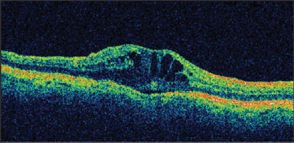

REPRINTED FROM OPHTHALMOLOGY, 115(1), LEVKOVITCH-VERBIN H, HABOT-WILNER Z, BURLA N, ET AL., INTRAOCULAR PRESSURE ELEVATION WITHIN THE FIRST 24 HOURS AFTER CATARACT SURGERY IN PATIENTS WITH GLAUCOMA OR EXFOLIATION SYNDROME, PP. 104-108, COPYRIGHT 2008, WITH PERMISSION FROM ELSEVIER.Cystoid macular edema (CME), among the most common causes of decreased vision after cataract surgery, is not a complication unique to glaucoma patients. However, the literature is replete with papers implicating prostaglandin analogs (PGAs) as an important factor contributing to CME. Latanoprost was approved by the FDA as the first PGA in 1996 for the treatment of glaucoma and ocular hypertension, and by the end of the decade there were several papers suggesting a relationship between CME and latanoprost.7-12 Moroi et al. published a case series correlating latanoprost usage to CME and CME's resolution after cessation of latanoprost.9 This relationship also exists postoperatively. Yeh et al. identified a 3% rate of postoperative, clinically significant CME within 1 month of uncomplicated phacoemulsification in patients with no known preoperative risk factors for CME other than the use of PGAs for IOP reduction (Figure 2). However, this rate is likely higher for eyes with additional risk factors for developing CME.10,13 With discontinuation of latanoprost and treatment with topical NSAIDs, all of Yeh's study patients had complete resolution of CME and return of visual acuity to normal within 1 month. Interestingly, patients chronically using latanoprost who were instructed to discontinue latanoprost 1 week prior to surgery avoided developing CME. The risk for postoperative CME is highest 30 to 90 days after phacoemulsification, but a small percentage of cases may occur after the initial 3 months.10,14

Figure 2. Postoperative CME in glaucoma patient.

IMAGE APPEARS COURTESY OF THE U.S. NAVAL MEDICAL CENTER, SAN DIEGO.The 2002 Binkhorst Lecture identified the preservative in latanoprost, benzalkonium chloride (BAK), as the most important etiologic factor contributing to CME.15 BAK is the preservative in approximately 70% of commercially produced eyedrops including Xalatan, Travatan, Azopt, Lumigan, Cosopt, Trusopt, and timolol maleate.16 This preservative is hypothesized to exacerbate the proinflammatory effect of topical antiglaucoma medications. Discontinuation of any nonessential drops containing this preservative should be considered during the treatment of CME.15